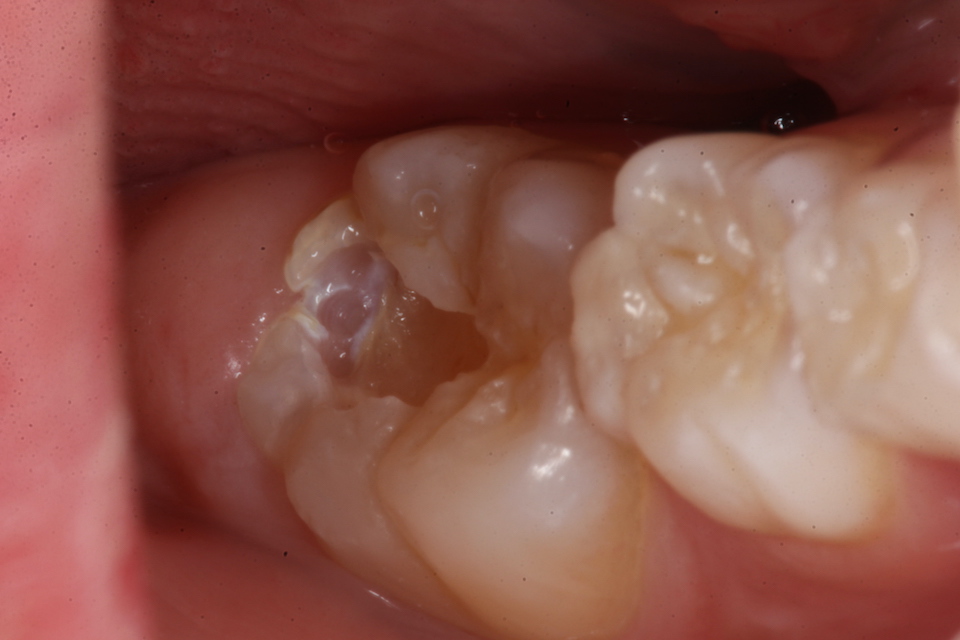

若い子の歯科治療シリーズ1.8(頬側面カリ… 2025.09.20